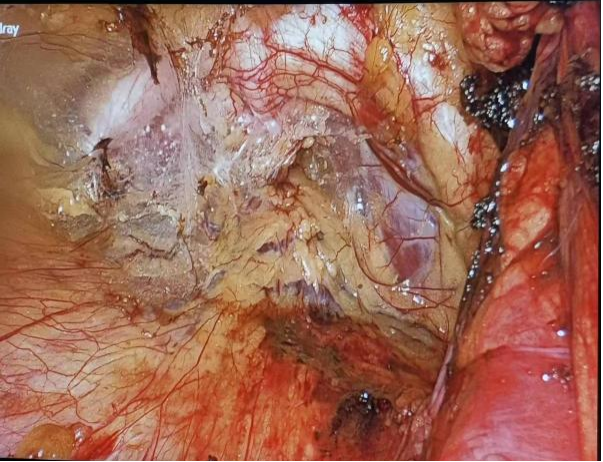

图1 术中场景